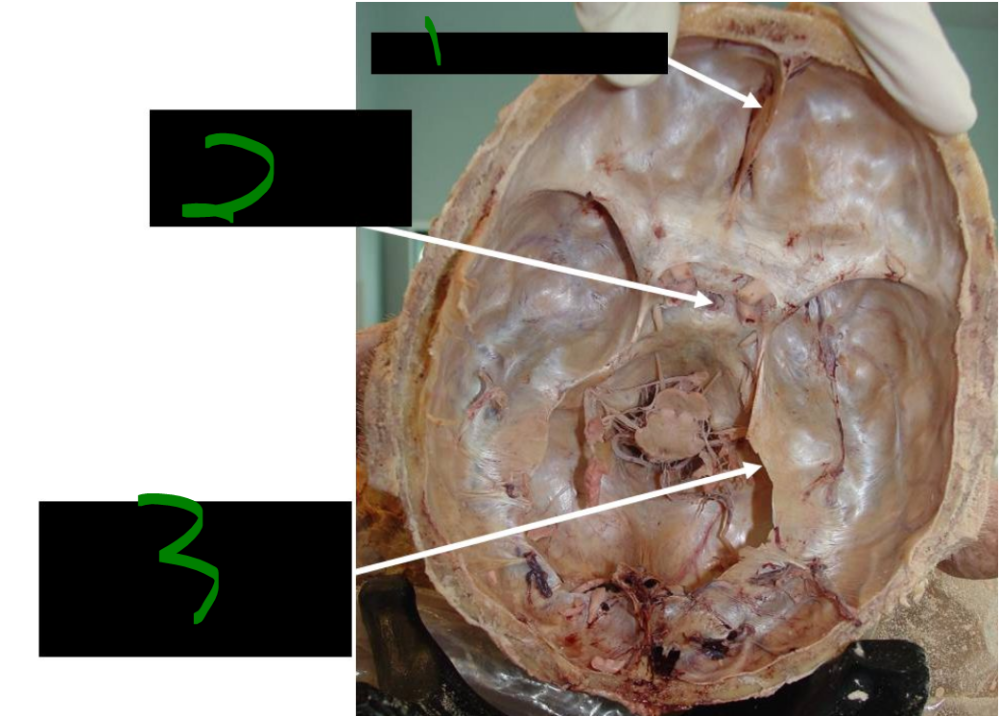

What is 1?

intracranial parts

73

card image

What is 2?

basilar artery

74

internal carotid a.

vertebral a.

72

What is 3?

posterior cerebral arteries

75